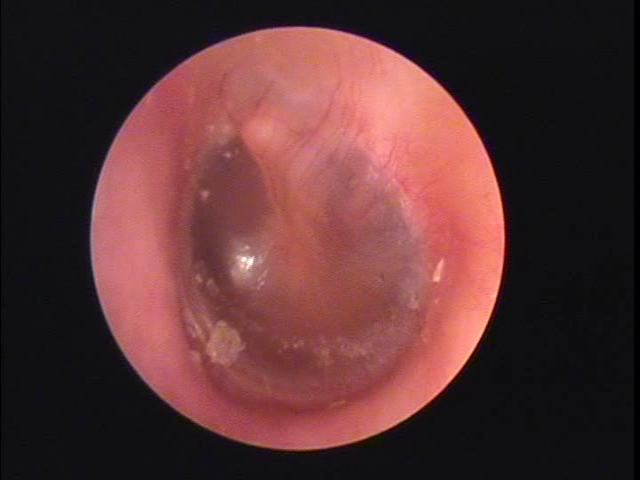

耳について | 千葉耳鼻咽喉科クリニック from chibacl.com